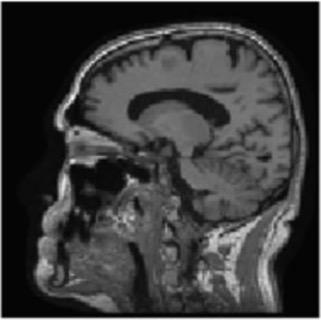

Image Pre-processing

Gray matter atrophy has been found to be responsible for MCI and AD progression (Apostolova et al., 2007). Pre-processing also standardizes the images. (Friston et al., 1994). Thus, pre-processing via segmentation and smoothing to capture just the gray matter of the MRI scans is necessary. The MRI scans were segmented using the Computational Anatomy Toolbox 12 (CAT 12) (Rajapakse et al., 1997) toolbox of MATLAB. These programs segmented the MRI images into grey matter, white matter, and cerebrospinal fluid. Figure 2 shows an unmodified MRI and a segmented MRI, which demonstrates the differences between them. After segmentation, the grey matter from each MRI scan was smoothed using the Statistical Parametric Mapping 12 (SPM12) (Friston et al, 1994) toolbox of MATLAB. These smoothed grey matter images were then sent for feature extraction.